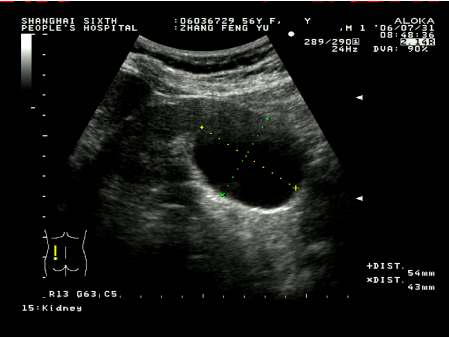

術前囊腫大小50mm左右

超聲引導下腎囊腫穿刺硬化治療具有簡單易行,患者少痛苦,復發率低,費用低等優點。這種方法是用超聲診斷儀事先選定穿刺點,設計好進針角度和進針深度,在局部麻醉下,用專用的穿刺探頭,根據已設定的角度和深度把直徑0.8毫米或1.2毫米的針插入囊腫,因為囊腫、針道和周圍臟器全部在超聲屏幕上看到,所以不會損傷周圍臟器,待抽凈囊液后,注入硬化劑,使硬化劑與囊腫內壁上皮接觸,達到硬化效果,數分鐘后把硬化劑抽出,拔出穿刺針,整個治療過程安全。在硬化治療后的早期(一個月內),一般說,囊腫上皮因硬化劑燒灼作用,會有滲出,一個月后開始漸漸吸收,三個月后明顯縮小,直至囊腫完全消失。